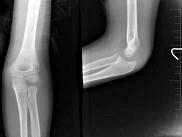

问题 8岁,男孩,外伤后感左肘关节肿痛,左肘关节正侧位摄片如图,下列哪项描述错误?(?)

选项 A.“八”字征 B.“X”线白线不连续 C.软组织肿胀 D.左肱骨小头骺线增宽 E.以上均正确

答案 D